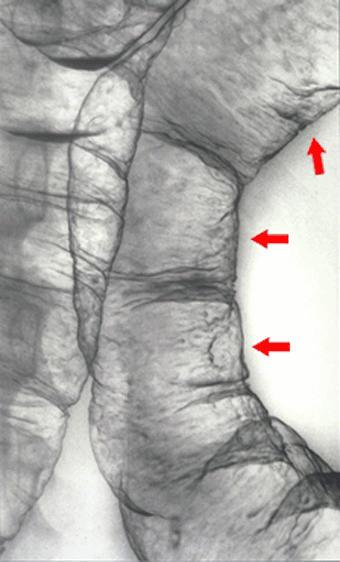

염증성 질환과 유사하고、다채로운 병변을 동반한 MLP(multiple lymphomatous polyposis)형의 소장 악성 림프종

악성 림프계종양/MLP형 악성 림프종

대장/2구역 이상의 대장에 걸치는 것

X-P